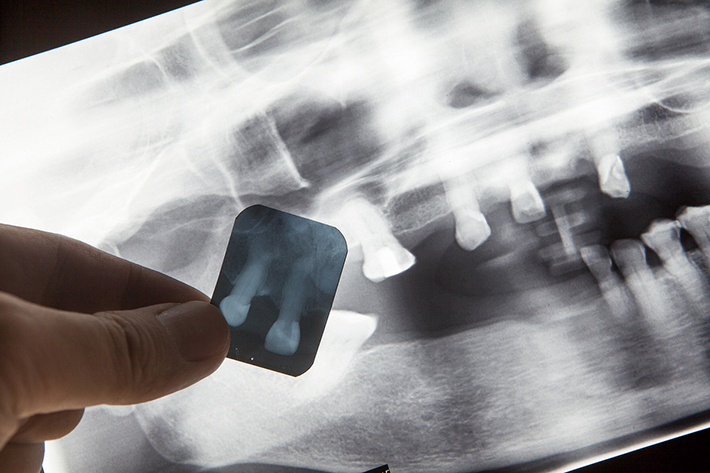

치과위생사의 방사선안전관리 시스템이 다소 미흡하다는 연구 결과가 발표돼 관련 교육 프로그램 개발과 제도 확충의 필요성이 제기됐다.

이번 연구는 ‘치과의료기관의 방사선안전관리시스템 실태’(저 이은경·주종욱·장계원)라는 제목으로 한국구강보건과학회 최신호에 게재됐다.

연구팀은 국내 일부 지역의 치과 병·의원, 대학병원 및 종합병원, 기타기관에 소속된 치과위생사를 대상으로 설문조사를 펼쳤으며, 이 가운데 196부의 응답지를 분석해 결과를 밝혔다.

연구 결과 방사선 안전관리자책임자가 소속 방사선 관계종사자들에게 주기적 교육을 시행하는지 여부에 대해 의료기관별로는 ‘대학병원 및 종합병원’이 65.0%로 가장 높았고 ‘치과병원’ 30.3%, ‘치과의원’ 28.9%의 순으로 나타났다. 이어 영상검사 정당화 가이드라인 여부는 ‘대학병원 및 종합병원’ 55.0%, ‘치과병원’ 42.4%, ‘치과의원’ 25.2%를 기록했다.

이 밖에 치과의원의 경우 임상화질 평가표 보유, 화질관리 일지 작성 여부, 진단용 방사선 발생장치의 선량과 진단참고수준과의 비교 등 15개 부문 중 과반인 9개 부문에서 타 기관 대비 낮은 수치를 기록했다. 또한 치과병원은 환자에게 방사선 장해 방어용 기구 사용 여부, 이동형 진단용 방사선 발생장치 사용 시 방사선 방어칸막이 사용 여부에서 가장 낮은 수치를 기록했다.

이 밖에 연구팀은 치과위생사의 결혼 여부 및 학력에 따른 방사선 안전관리시스템 실태를 조사했다.

결과에 따르면 치과위생사의 방사선 안전관리시스템 실태는 기혼과 석사 이상의 고학력일수록 높은 결과가 나타난 것으로 확인됐다.

세부적으로 기혼과 석사 이상 고학력 치과위생사는 ‘방사선 안전관리자책임자가 소속 방사선 관계종사자에게 주기적인 교육을 시행하는 경우’, ‘환자에게 방사선 장해 방어용 기구를 사용하는 경우’, ‘개인피폭선량계를 올바르게 착용하는 경우’, ‘비상상황 시 대처 프로토콜이 있는 경우’ 등 대부분의 분야에서 대조군보다 높은 수준을 기록했다.

연구팀은 “연구 결과 치과위생사의 치과의료기관 방사선안전관리 시스템이 미흡한 것으로 드러났다”며 “인식과 실천율을 개선하기 위한 방사선안전관리의 정기적 교육, 보수교육 등 프로그램 개발과 법적 제도 마련이 필요하다”고 강조했다.